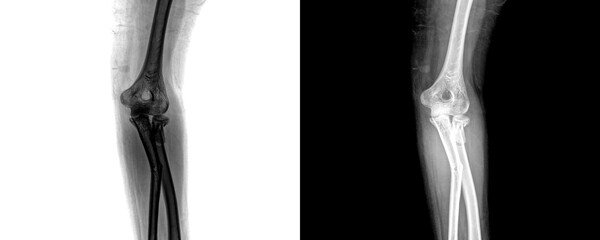

Podobny obraz Medical Elbow Anterior View X-Ray Radiograph Illustrating...